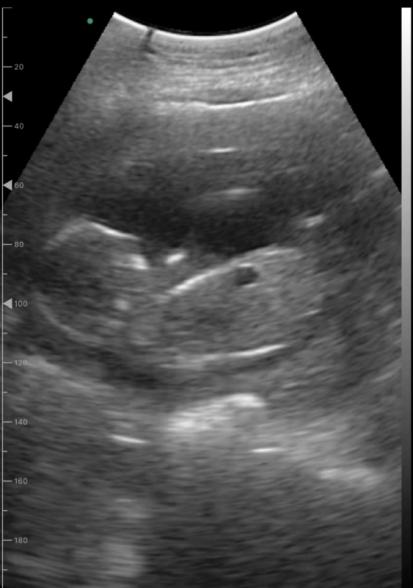

現在妊娠17週。自宅で家庭用エコーを使って毎日胎児を確認しています。

心臓が動いていることにホッとしていますが、時折写真のような黒くて丸い影が映ることがあります。今までの健診では特に指摘を受けたことはありません。次回の健診が一ヶ月後のため心配で、、。これは何か分かりますでしょうか?

実際に拝見していませんので、はっきりとしたことは明言できませんが、もしかすると、胃や腸に見られる空気なのかもしれませんね。特に健診で何も指摘されていないのでしたら、ご心配なものではないと思いますよ。また気になるようでしたら、健診の際にでもご確認なさってくださいね。